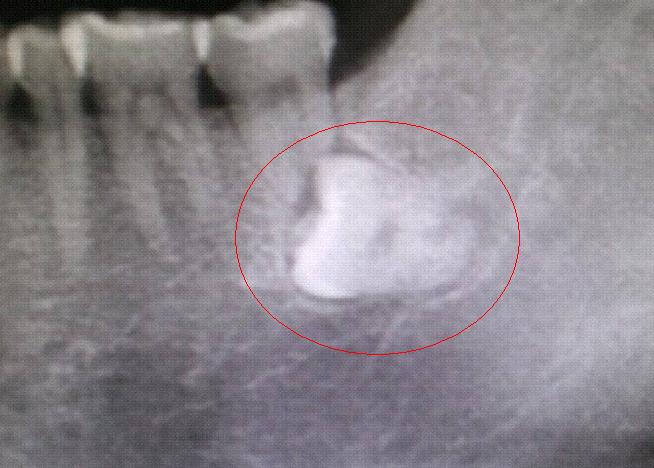

痛苦的趋使下,我才去牙科做了检查。结果......牙齿倒在牙龈中,彻底长不出来了,医生说:必须拔掉!

再想起网上描述的拔牙更是四肢无力:打麻药、牙肉切开、锤子敲分牙齿、拔出、缝合。打三天吊针、脸会肿、无法说话、只能吃流质食品......想想就冒冷汗!